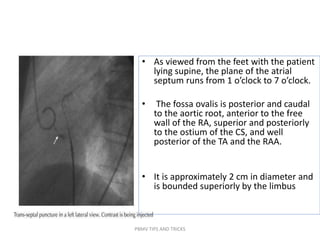

• As viewed from the feet with the patient

lying supine, the plane of the atrial

septum runs from 1 o’clock to 7 o’clock.

• The fossa ovalis is posterior and caudal

to the aortic root, anterior to the free

wall of the RA, superior and posteriorly

to the ostium of the CS, and well

posterior of the TA and the RAA.

• It is approximately 2 cm in diameter and

is bounded superiorly by the limbus

PBMV TIPS AND TRICKS